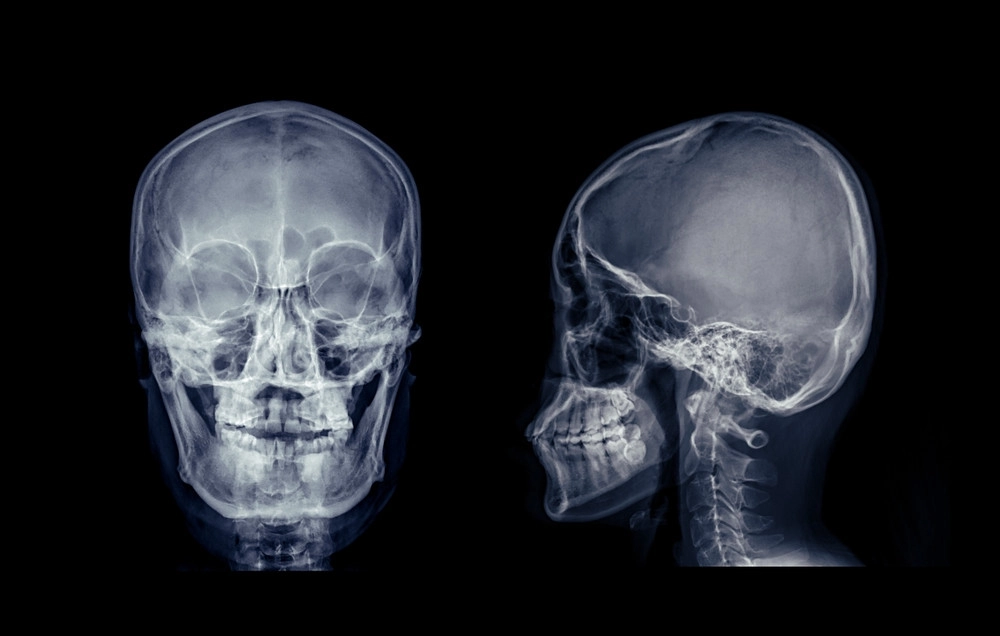

La fracture du rocher, ou fracture pétreuse de l’os temporal, est une lésion rare mais sérieuse qui touche l’un des os les plus complexes du crâne. Situé à la base du crâne, le rocher abrite des structures vitales, comme l’oreille interne et des nerfs essentiels, ce qui rend ce type de fracture particulièrement préoccupant. Comprendre ses symptômes et ses risques est crucial pour une prise en charge rapide et efficace.

L’os temporal se compose de plusieurs parties, dont le rocher, une section dense et pyramidale située à la base du crâne. Il protège l’oreille interne, les nerfs crâniens et les vaisseaux sanguins importants. Une fracture du rocher survient généralement lors de traumatismes crâniens sévères, comme un accident de la route, une chute de hauteur ou un choc violent à la tête.